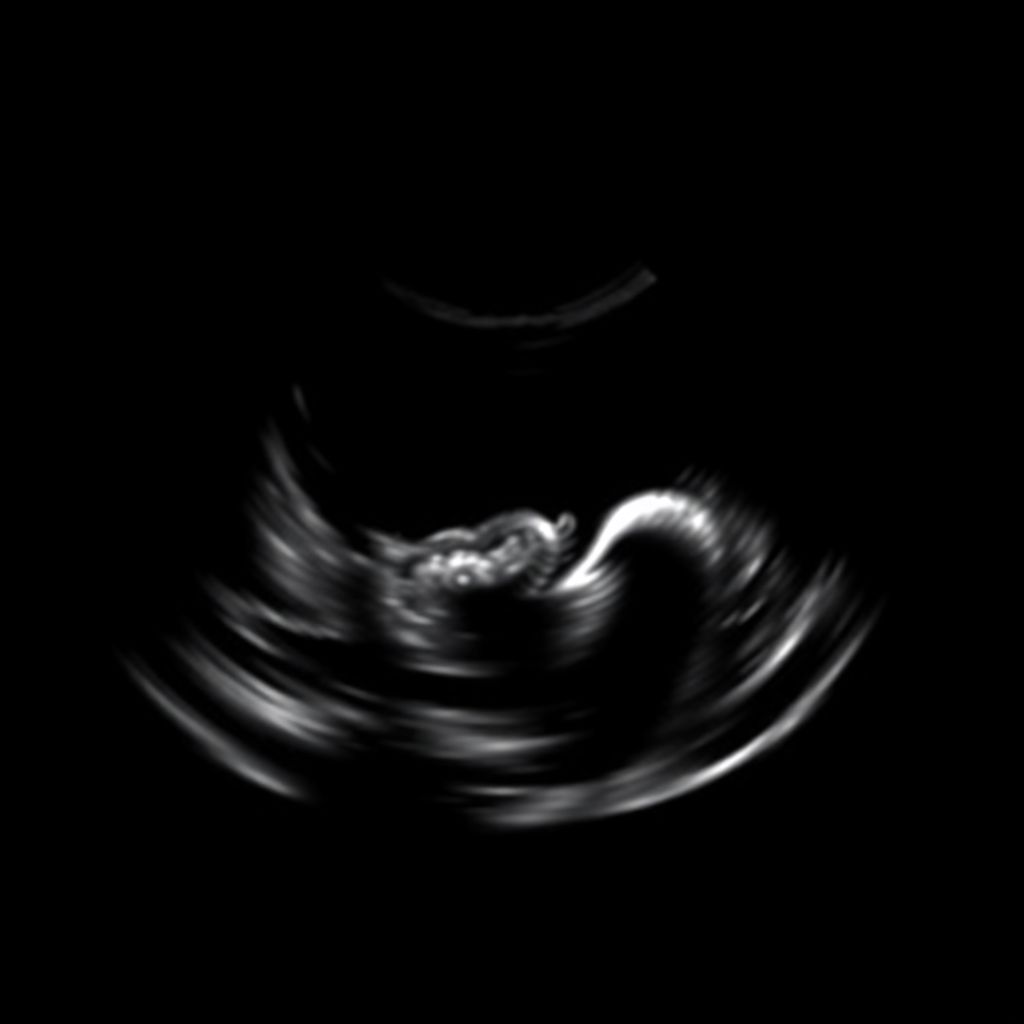

На ранних сроках беременности, особенно до 12-й недели, срок определяется по размеру эмбриона — чаще всего по копчико-теменному размеру (КТР). Этот параметр является самым надежным для уточнения гестационного возраста, поскольку эмбрион развивается по очень стабильному графику. Уже на 6–7 неделе при помощи трансвагинального датчика можно зафиксировать сердцебиение и измерить КТР, что делает УЗИ на ранних сроках беременности ключевым инструментом для диагностики.

Современные протоколы рекомендуют проводить первое УЗИ при беременности в период с 6 по 9 неделю, особенно если дата последней менструации неизвестна или имеются нерегулярные циклы. Тогда определение недели беременности УЗИ является более точным, чем расчет по календарю. После 12-й недели точность снижается, так как на развитие плода начинают влиять индивидуальные факторы.

В 2025 году в клинической практике активно применяются аналитические модули искусственного интеллекта, которые интегрированы в ультразвуковое оборудование. Эти системы автоматически определяют срок беременности по УЗИ с точностью до 2–3 дней, что существенно превосходит ручные расчеты. Кроме того, высокочастотные датчики позволяют визуализировать даже минимальные отклонения в развитии эмбриона, что важно для ранней диагностики патологий и уточнения срока.

В современных перинатальных центрах, например, в Москве и Санкт-Петербурге, определение срока беременности осуществляется на аппаратах экспертного класса. Ультразвуковое исследование часто проводится уже в течение первой недели после положительного теста, особенно у женщин с ЭКО или нерегулярным циклом. В таких случаях вопрос «как определить срок беременности по УЗИ» решается с помощью трансвагинального обследования, которое обеспечивает визуализацию плодного яйца уже на 4–5 неделе.